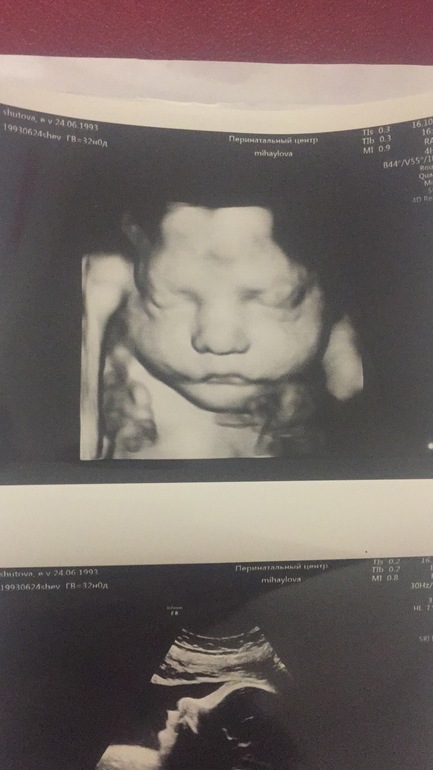

я делала дважды) не прлучалось, лежал плохо. а потом соучайно вдруг сделали фотку на 34-35 уже примерно неделе) по мне-интересно, но все равно непонятно же, как будет выглядеть

у меня на узи вон какой нос был)